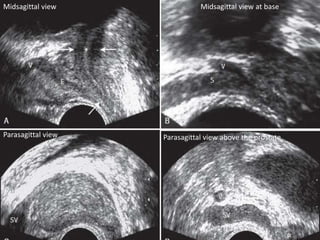

Midsagittal view Midsagittal view at base

Parasagittal view above the prostateParasagittal view

above base atmidgland level at lower third of prostate below apex of prostate

Midsagittal view Midsagittalview at base Parasagittal view above the prostateParasagittal view